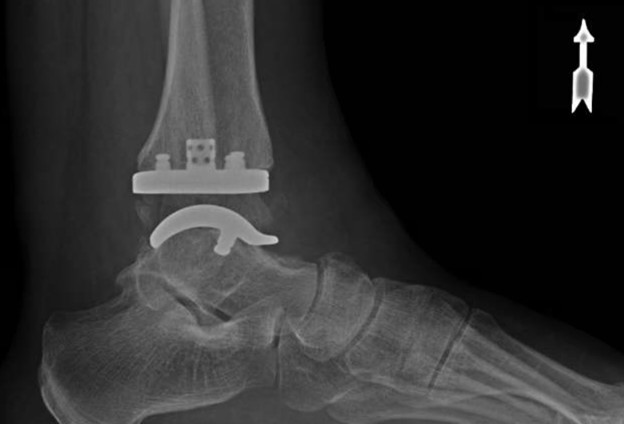

Led by Dr. Vinod Panchbhavi, a world-renowned orthopaedic foot and ankle surgeon, our fellowship covers all aspects of foot and ankle surgery including trauma, reconstruction, ligament and tendon injuries, arthroscopy, arthroplasty, and midfoot and

where he performed around 100 cases of total ankle arthroplasty. His other clinical interests include minimally invasive surgery and foot and ankle trauma.

- Clinical exposure: Between the three attendings, you will have between 500-800 cases for the year, covering all aspects of foot and ankle surgery. Each attending has his own operating style and have different backgrounds so you will be exposed to

a variety of techniques and methods. In addition, UTMB provides medical care to the Texas Department of Criminal Justice, which allows for exposure to some of the most complex pathology possible. Finally, the fellowship is very hands-on and graduated

autonomy is given early and often.